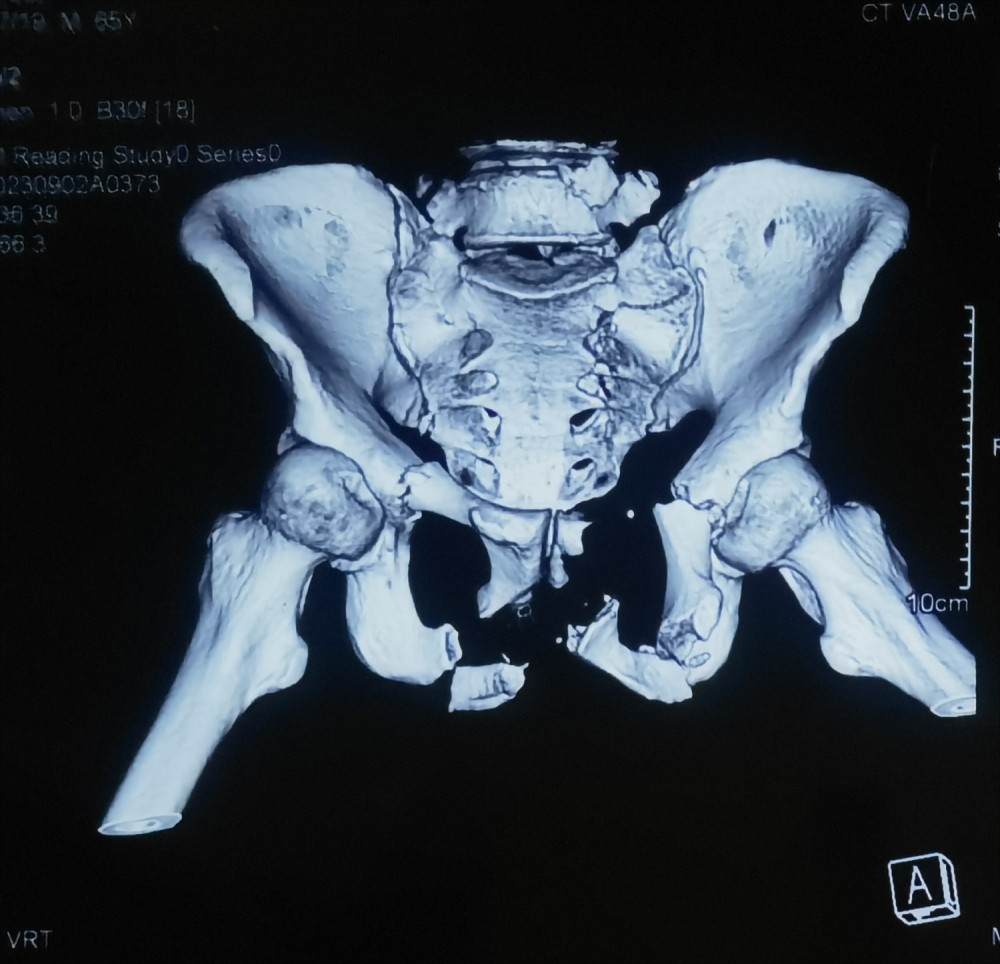

考虑患者骨盆骨折合并盆腔脏器损伤可能性极高,立刻给予患者补液抗休克并留置导尿,但未见尿液引出,随即联系医技科室开辟绿色通道并护送患者急行腹部CT、彩超、心电图等相关检查,并请普通外科紧急会诊,吕冰副主任医师为患者进行尿道逆行造影,结果显示,尿道断裂、膀胱破裂。正是因为于成涌医师的准确判断以及吕冰医师的专业支持,为接下来的抢救工作赢得了黄金时间。

尿道逆行造影X光片